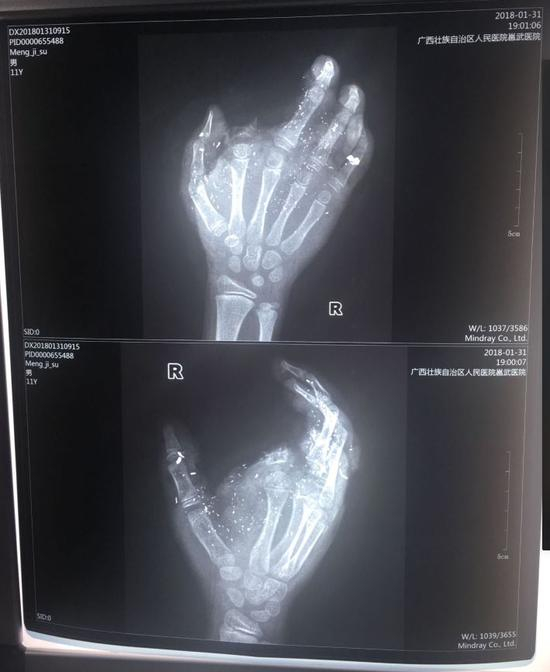

邕武医院急诊科兰天兵医生介绍,孩子送来时伤势很重。右手食指被炸没了,拇指、中指、无名指也都炸伤,失去了供血,手掌皮肤被炸得稀烂。经CT检查,右眼内有2块手机碎片。

记者从医院了解到,孩子断的那根手指已经植不回去了。目前手术通过血管移植,让孩子损伤的另外3个手指恢复了血供,预计今后不会对功能造成太大影响。